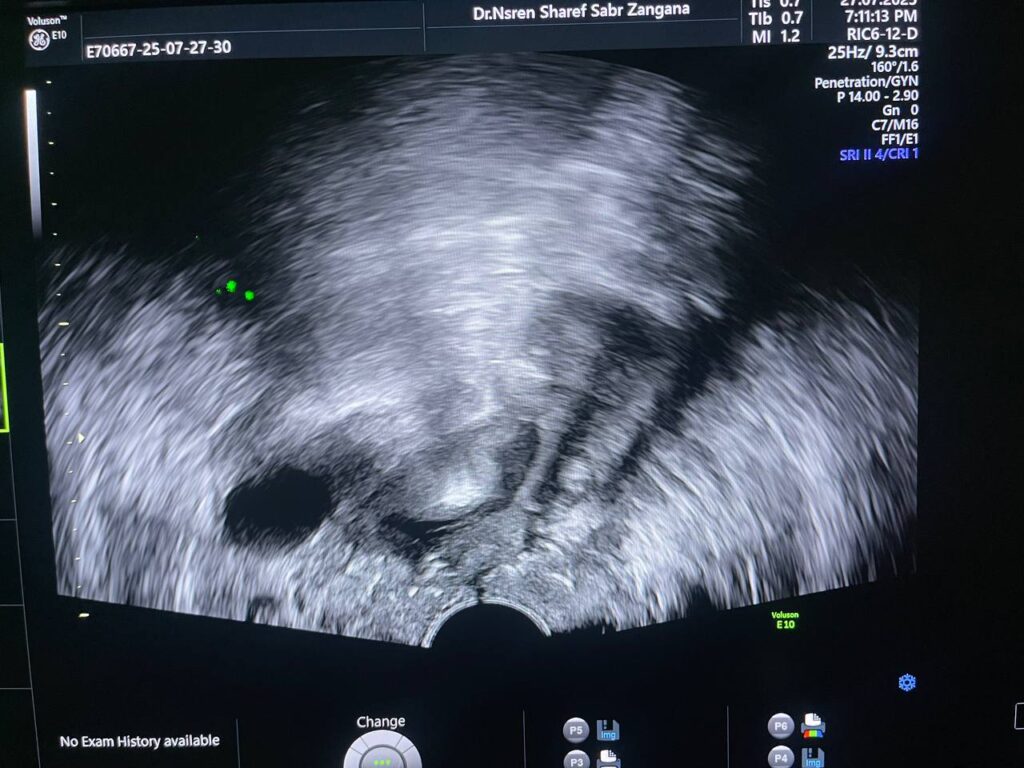

Post Hystercetomy Abcess Formation

Uterus removed , with presence of collected heterogenous fluid 27x14mm in the bed , contain air , could be abscess ? please for further study to exclude other pathology